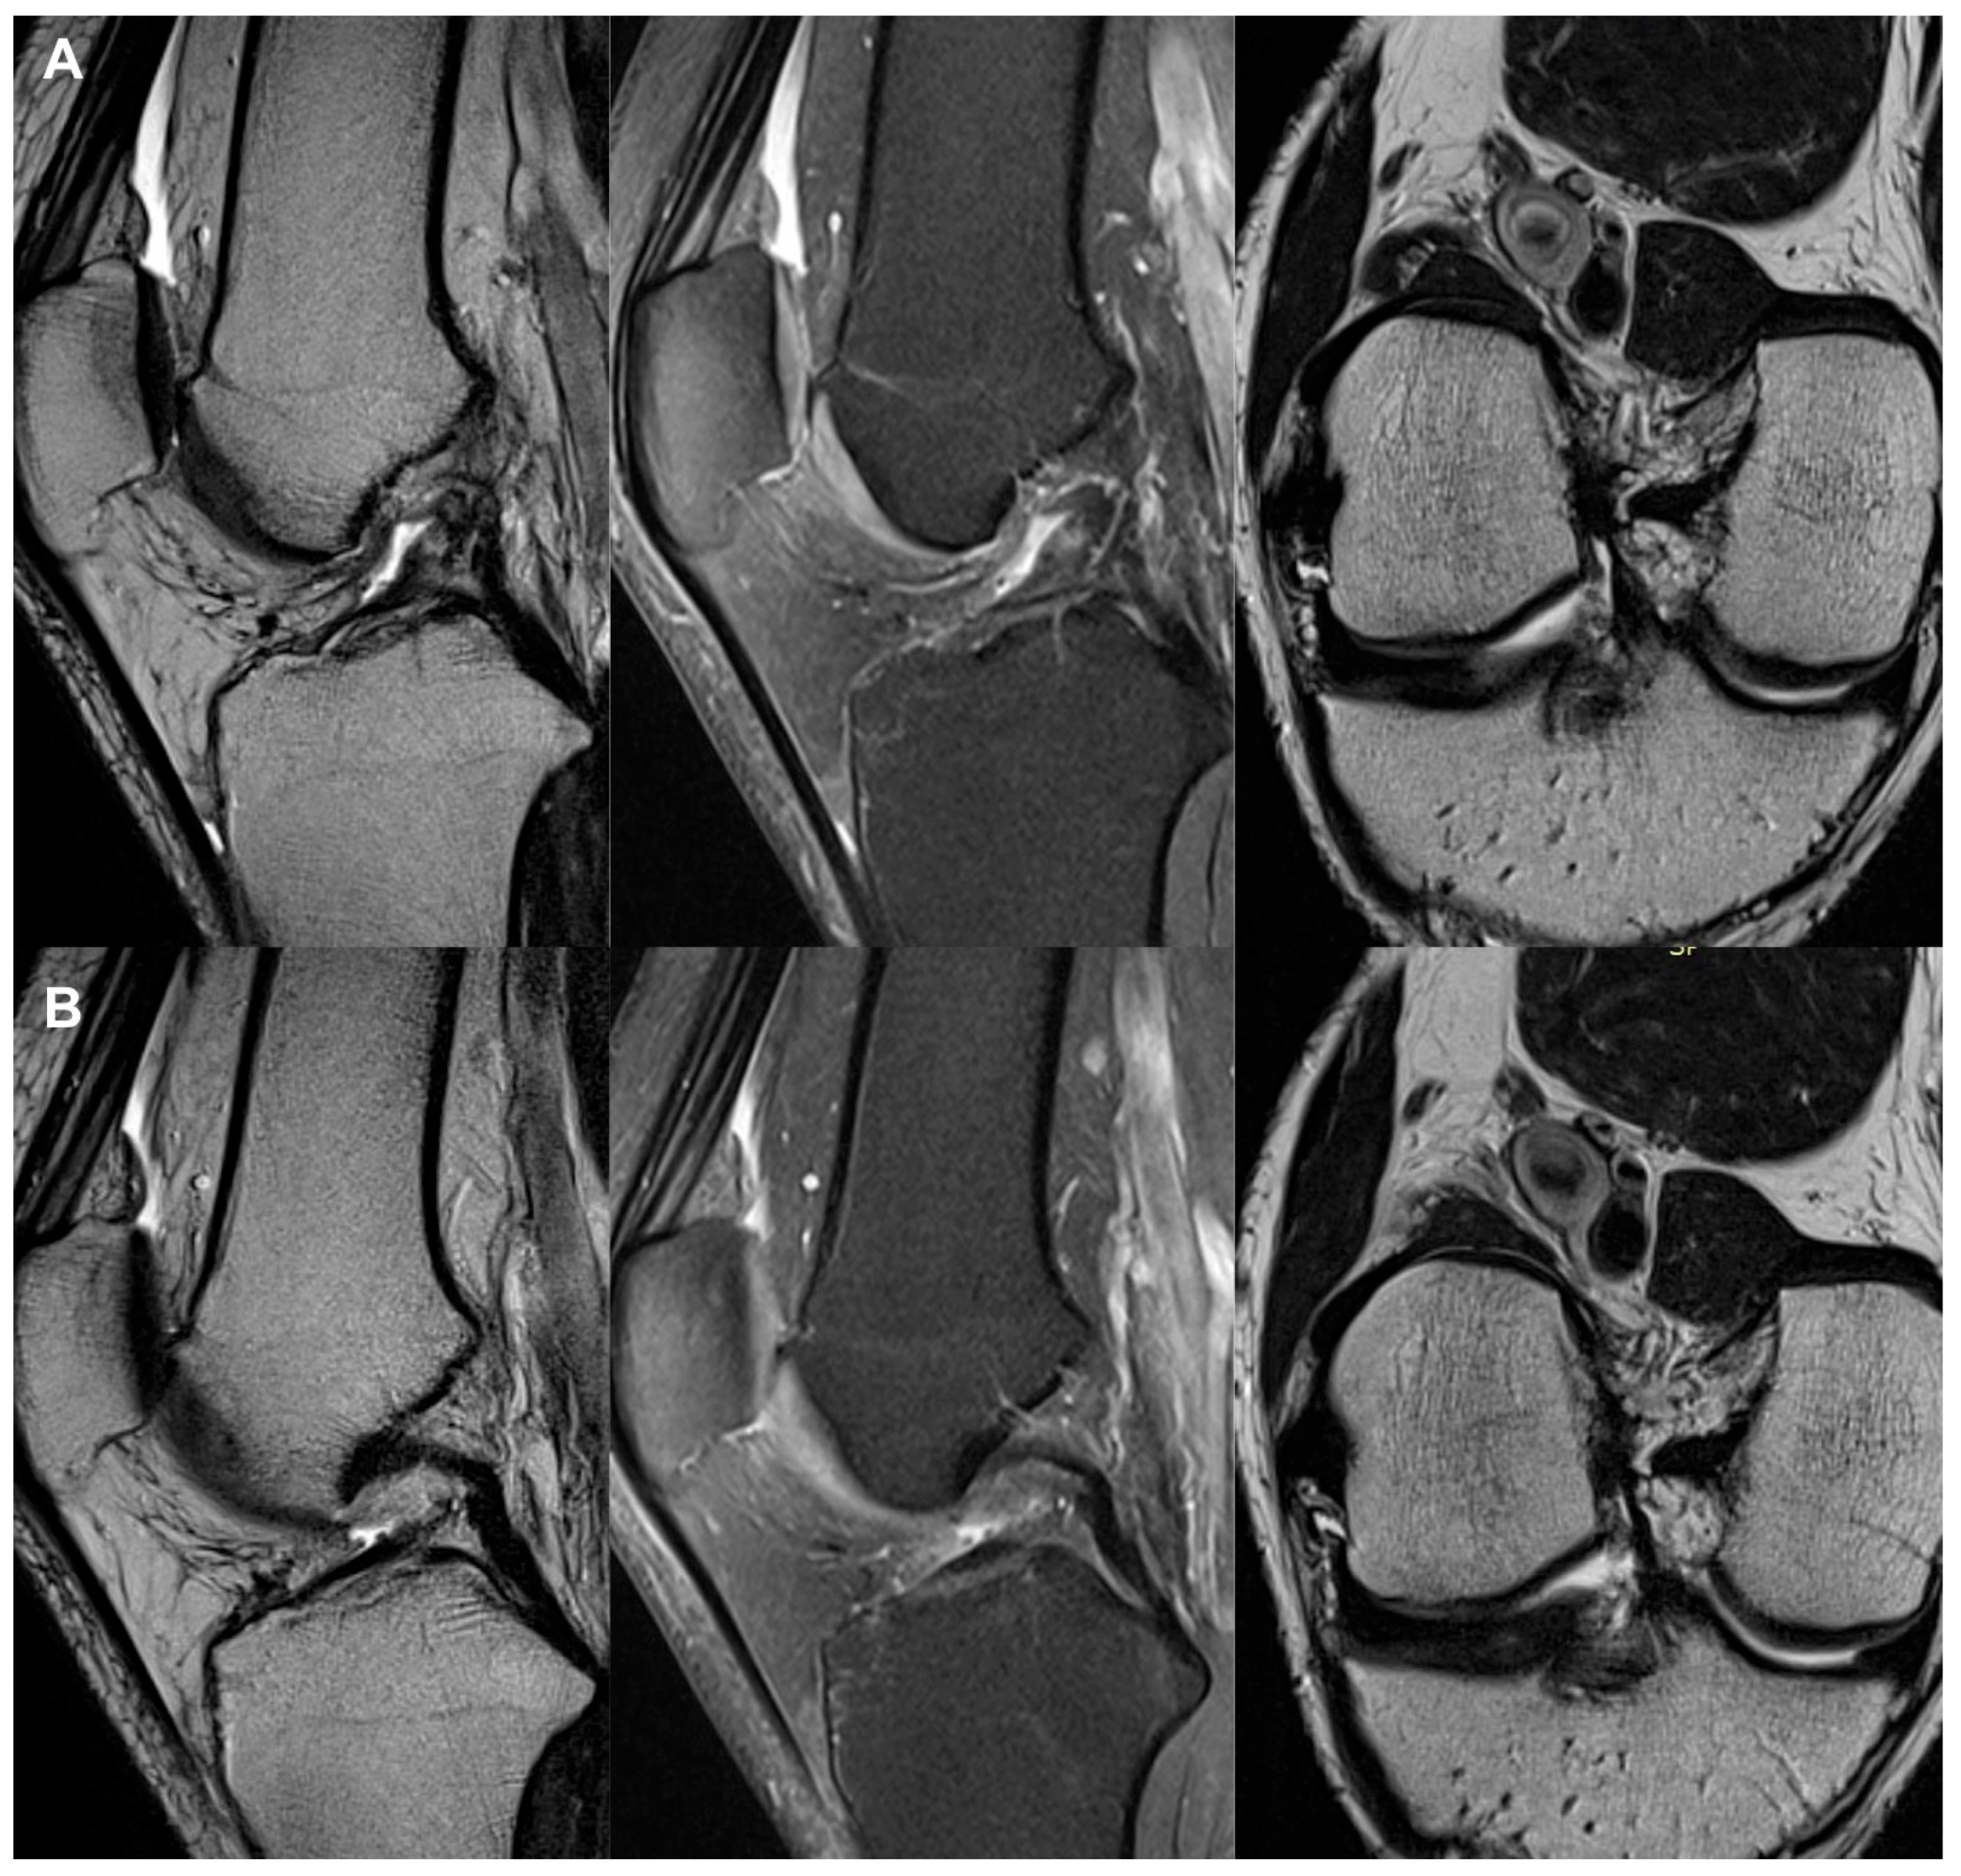

All the MRI analyses in the treatment group, except one, revealed a healthy, intact ACL with a normal signal, as shown in Figure 2, Figure 3, Figure 4, Figure 5, Figure 6, Figure 7 and Figure 8. Figure 9 shows an example of an unregenerated ACL in a patient from the control group.

Figure 2.

The same knee MRI scans of a patient with an anterior cruciate ligament tear and concomitant lateral tibia condyle fracture before treatment (A) and corresponding MRI scans of the same patient after nanosurgery treatment with an RP-hCM ACL injection (B). The time to return to regular daily activities with full weight-bearing on the injured limb without instability and pain was 9 weeks.